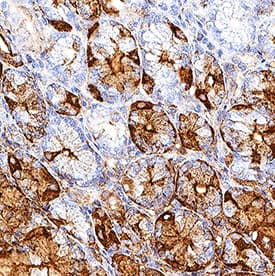

Pepsinogen A5/PGA5 antibody in Human Stomach by Immunohistochemistry (IHC-P).

Pepsinogen A5/PGA5 in Human Stomach.

Pepsinogen A5/PGA5 was detected in immersion fixed paraffin-embedded sections of human stomach using Mouse Anti-Human Pepsinogen A5/PGA5 Monoclonal Antibody (Catalog # MAB8457) at 0.5 µg/mL for 1 hour at room temperature followed by incubation with the Anti-Mouse IgG VisUCyte™ HRP Polymer Antibody (Catalog # VC001). Before incubation with the primary antibody, tissue was subjected to heat-induced epitope retrieval using Antigen Retrieval Reagent-Basic (Catalog # CTS013). Tissue was stained using DAB (brown) and counterstained with hematoxylin (blue). Specific staining was localized to intestinal glands. View our protocol for IHC Staining with VisUCyte HRP Polymer Detection Reagents.